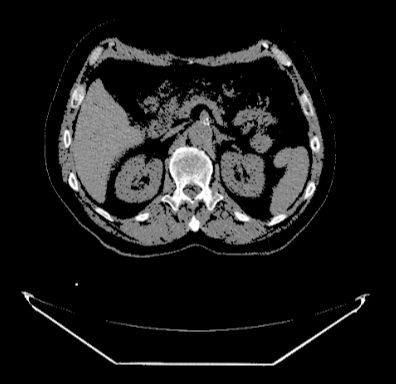

DcmViewer可以设置某个CT值区间,使在这个CT值区间之外的颜色透明,而在这个区间之内的颜色绝对的不透明。 滑动滑块可以改变CT值区间。

在2(1)中讲到, CT切片图像所有的CT值,拿样例举例,样例中一个CT值可表示为16位无符号整数,那么它代表的数可以覆盖的范围是 , 如果一个CT值可表示为16位有符号整数, 那么它代表的数可以覆盖的范围是 -32768 到 32768。

比如,把样例中的颜色不透明区间设置为 100-32768。

则CT切片图像中CT值少于100的颜色将全部透明(即不显示),仅显示CT切片图像中CT值在100-32768之间的颜色。